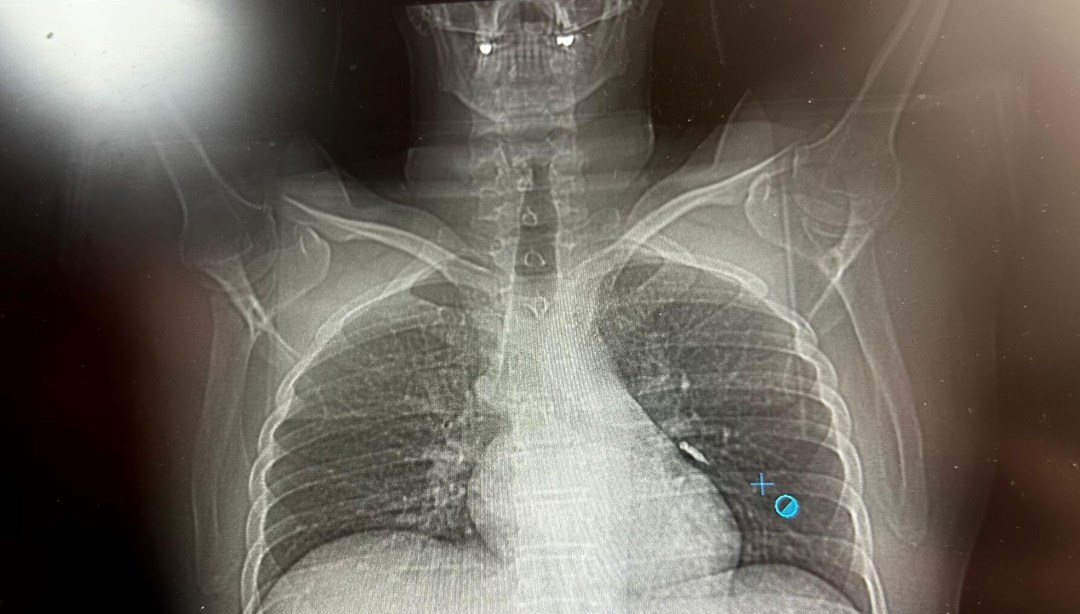

‘ın İpekyolu ilçesinde ikamet eden F.T. isimli hasta, dış merkezli bir diş kliniğinde implant tedavisi gördüğü sırada, implant vidası yanlışlıkla soluk borusuna kaçtı.

Nefes borusuna kaçan vida nedeniyle hasta, ileri tetkik ve tedavi amacıyla Van Eğitim ve Araştırma Hastanesi’ne sevk edildi.

Hastaya bronkoskopi işlemi uygulandı. Sol akciğerin üst lobunda saplanmış şekilde tespit edilen vida, vidalı yapısı ve bulunduğu konum nedeniyle güçlükle yerinden oynatılabildi.

Yapılan uzun ve titiz müdahale sonrası vida yerinden çıkarılamasa da hasta bir süre sonra geçirdiği öksürükle birlikte implant vidasını midesine gönderdi. Vida, daha sonra doğal yollarla vücuttan atıldı.